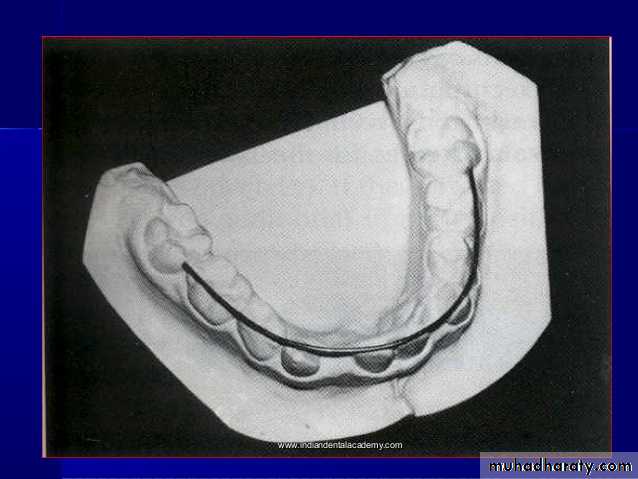

Cast analysis1.Arch Length &Arch Perimeter analysis

• dental space Analysis : Arch Required Arch Available

Arch space= Arch Required - Arch Available

Requirements to do cast analysis

• Well prepared study models• Vernier calipers

• Divider

• Ruler

• Brass wire